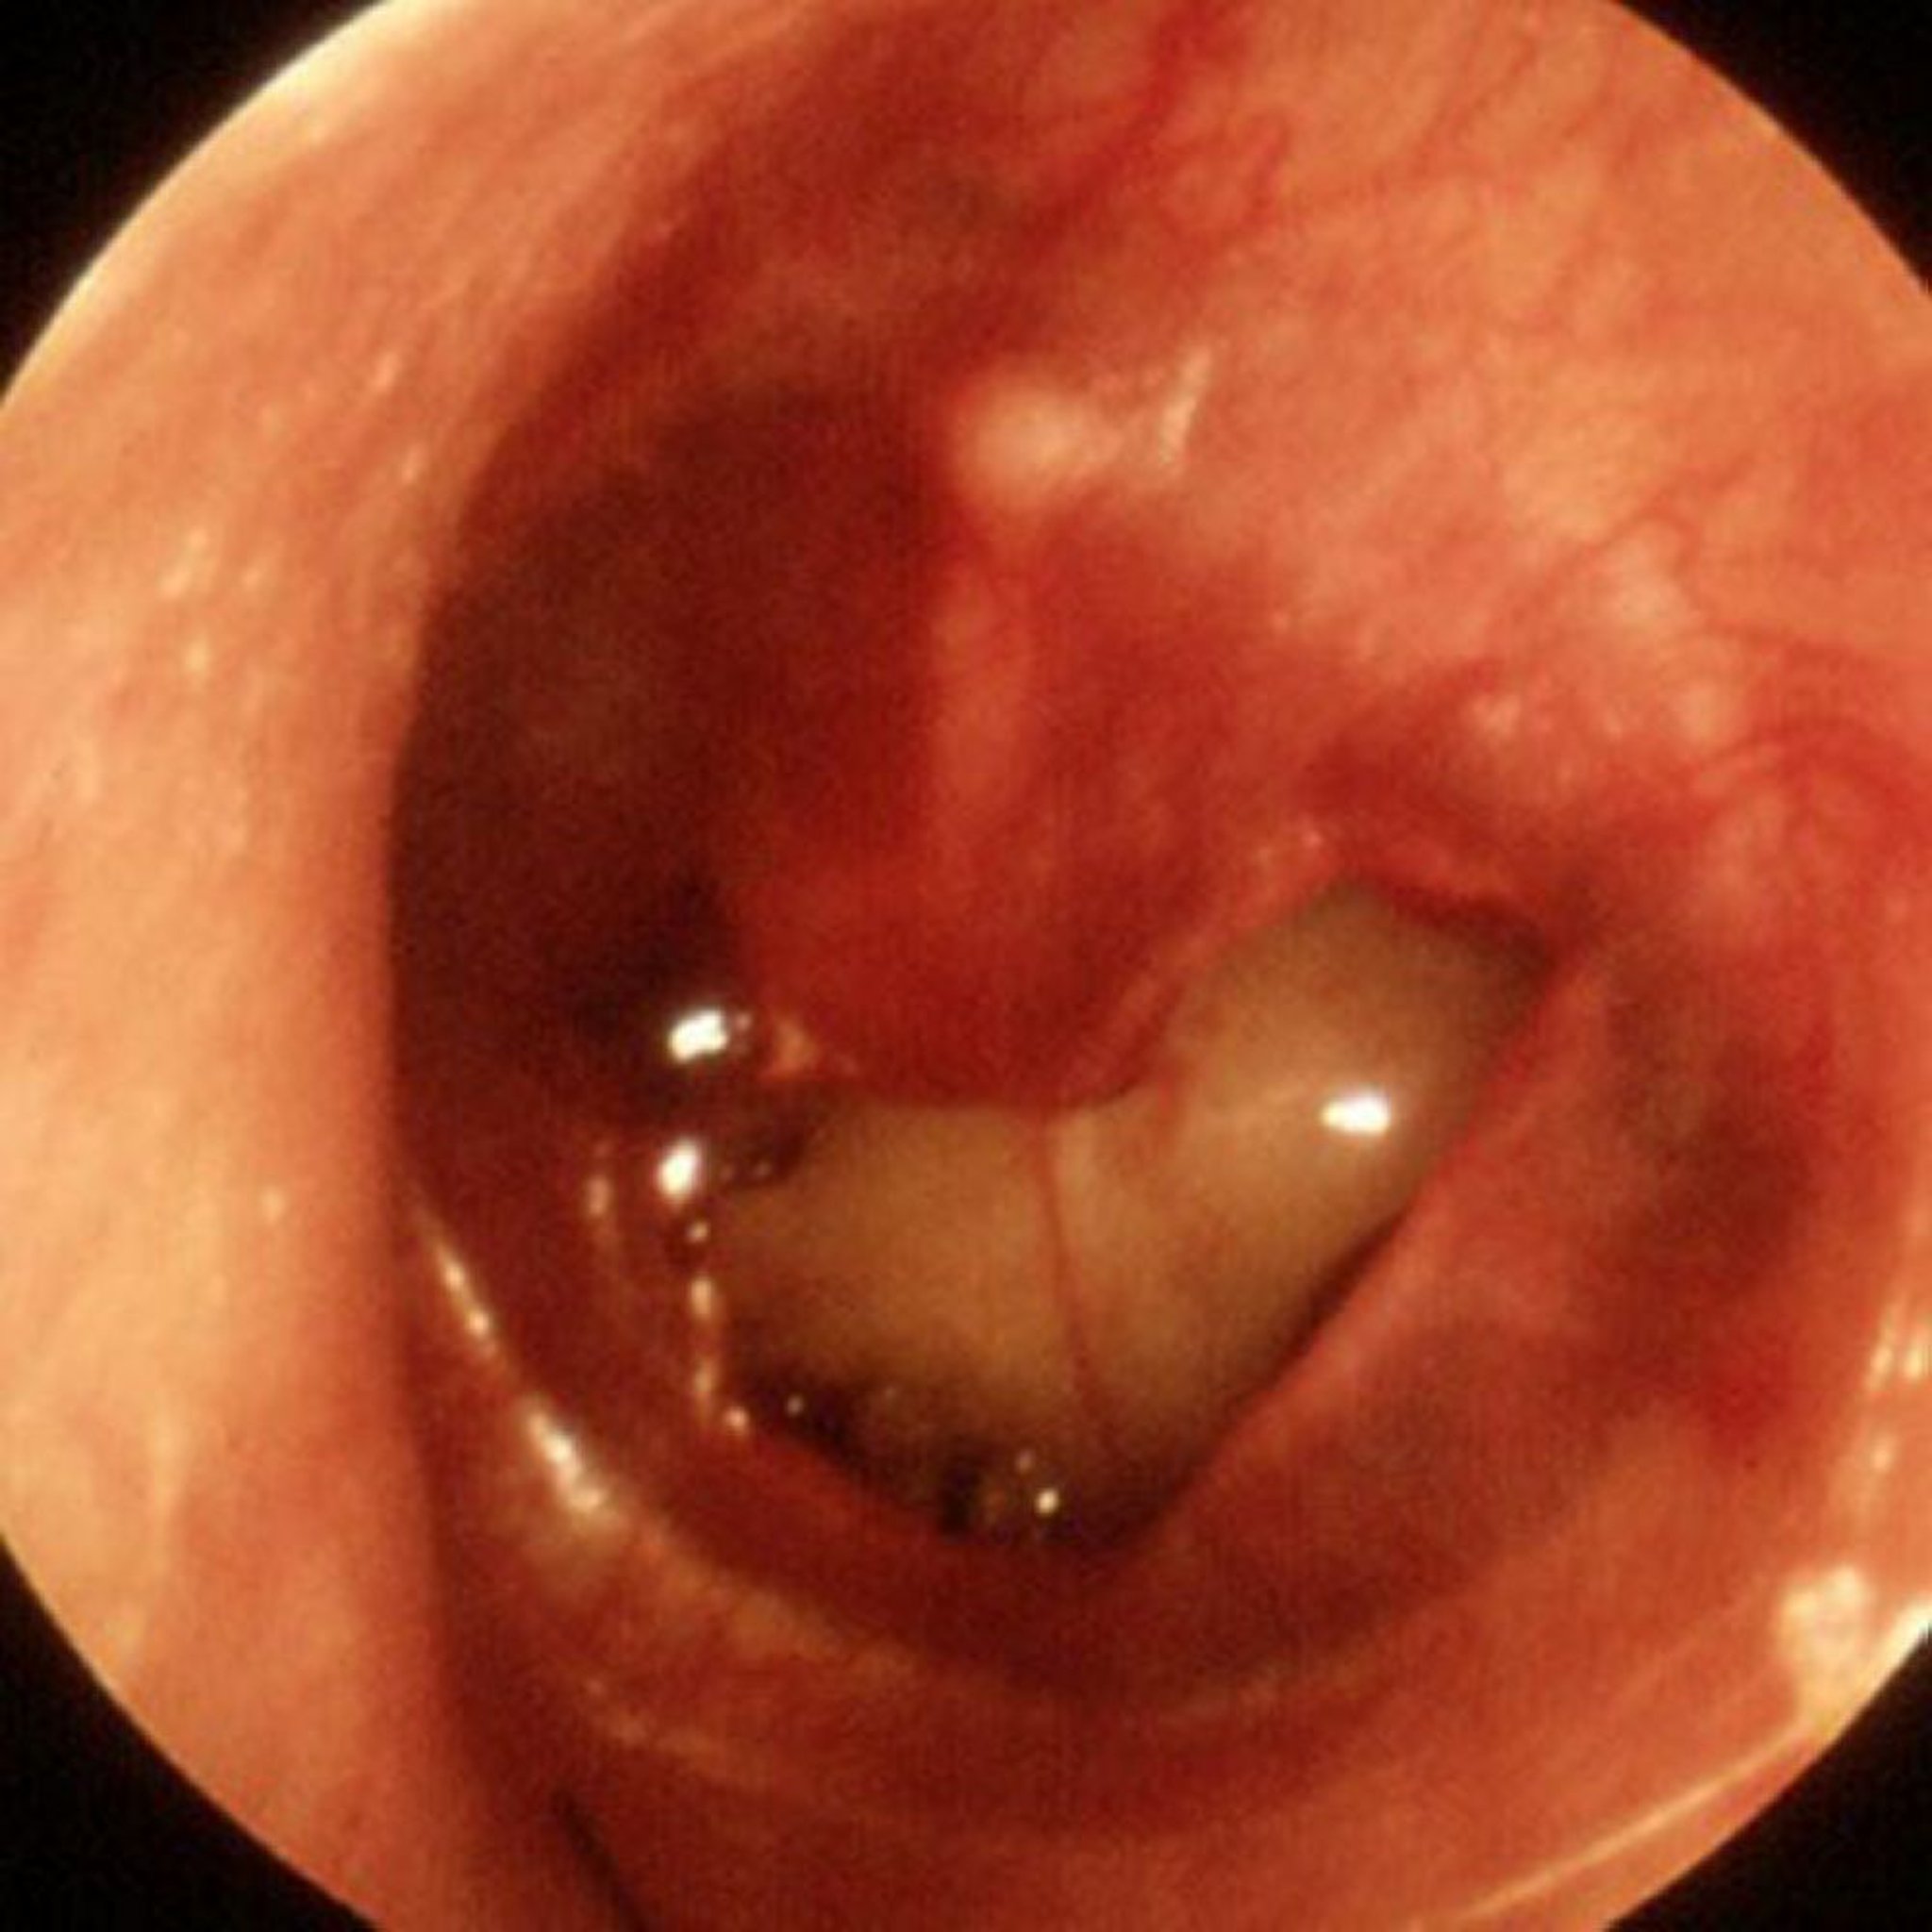

Thủng màng nhĩ do chấn thương

Có thể thấy một lỗ thủng lớn do chấn thương trong hình này.

Hình ảnh do Piet van Hasselt, MD cung cấp.